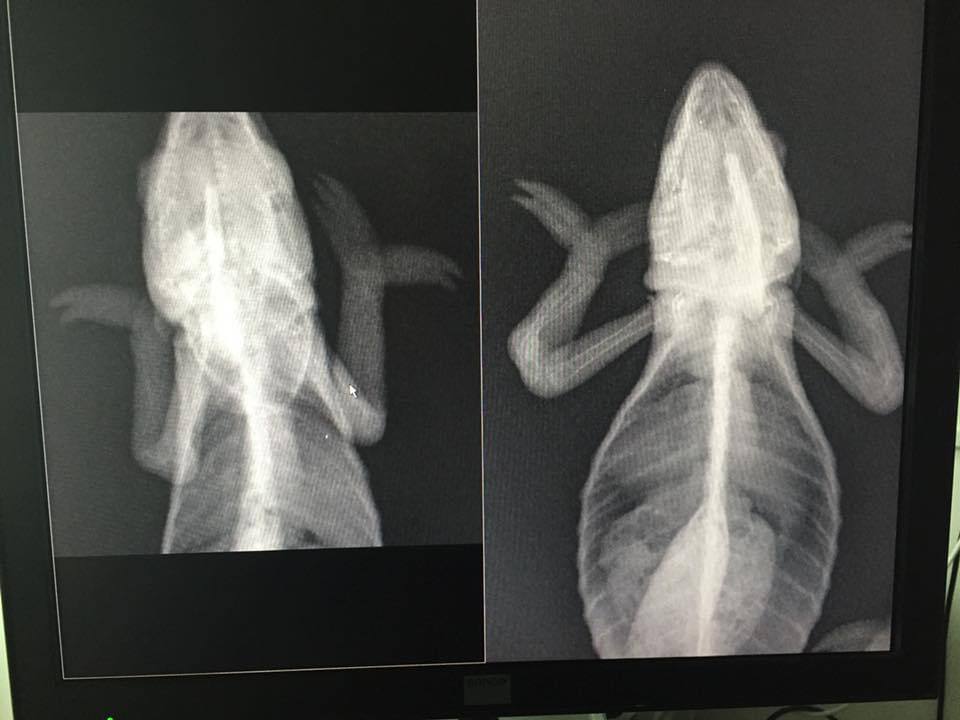

A Word About Impaction In Reptiles

A word about impaction in reptiles and a short case study example explaining why often cases of impaction can be mistaken for vitamin deficiency